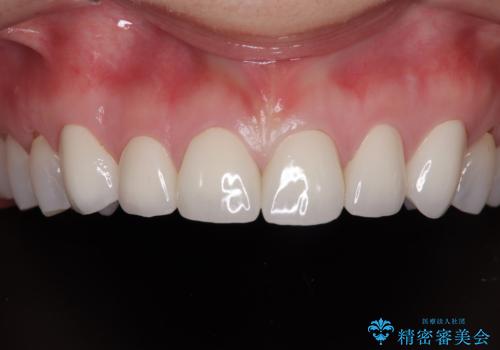

歯の神経は生きていますが、精度の高い被せもののため冷たいものがしみるなどの症状もなく、きれいになったと満足していました。